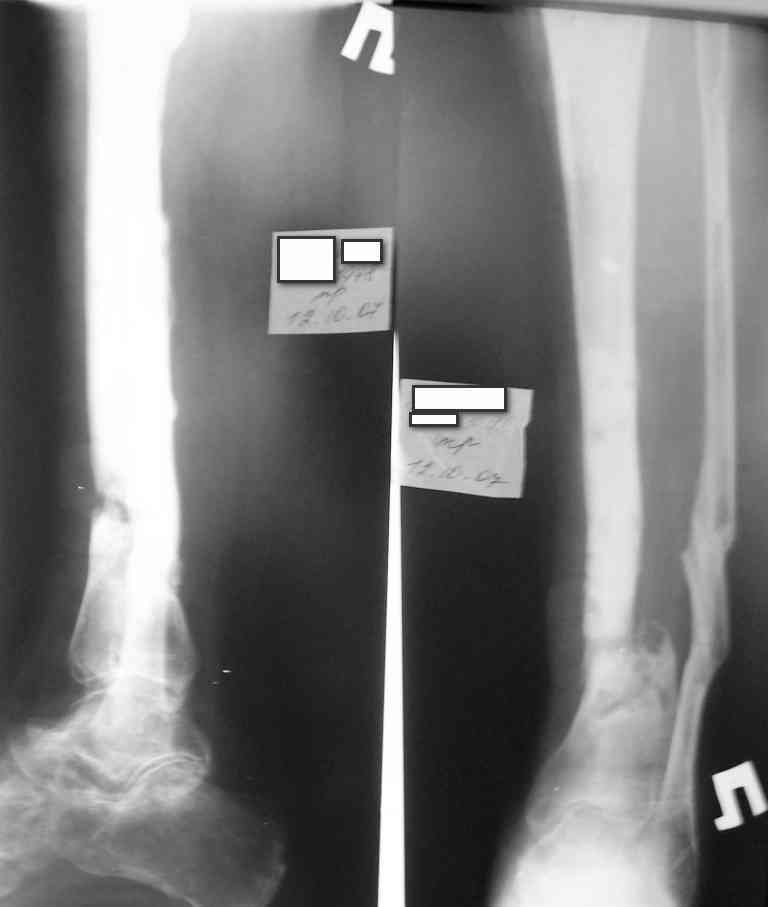

Укорочение конечности на 4,5-5,0 см., растройств чувствительности нет. При ходьбе конечность нагружает практически полностью при использовании тутора и ортопедической обуви. Внешний вид и R-гр. на фото. У больного еще пока сохранился настрой на лечение.